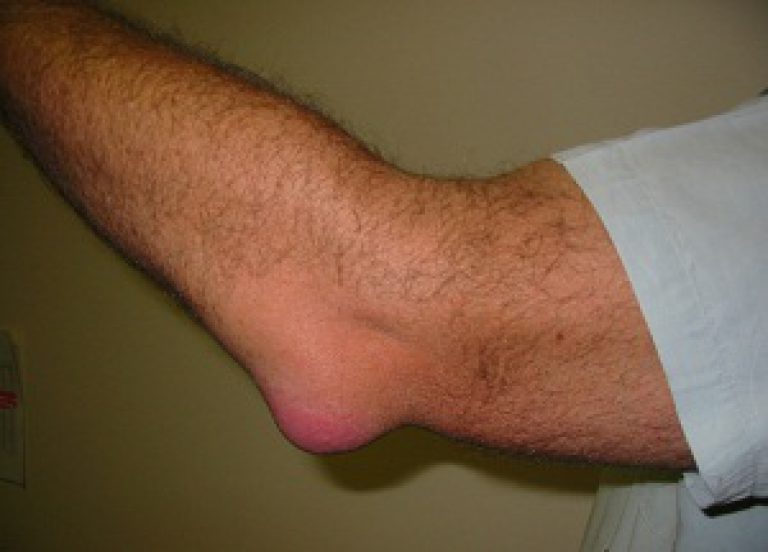

Фото артрита локтя:

- Гнойный артрит, его симптомы: повышение температуры, стремительно проявляющаяся интоксикация (тошнота, рвота, головокружение), припухлость непосредственно локтевого сустава. На месте дислокации недуга проявляется покраснение, кожа болезненная и горячая. Возможны болевые атаки, в острой форме протекания болезни эти атаки просто невыносимы.

- Отечность в области локтя, связанная с избыточным содержанием внутрисуставной жидкости;

- Поверхность кожи над локтевым суставом красная;